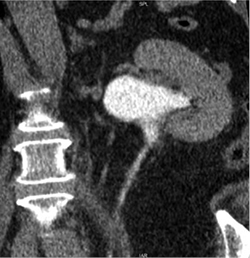

2019 m. gegužės 7 d. (praėjus apie 6 mėn. po operacijos) atlikta kompiuterinė tomografija (4 pav. B). Kairiojo inksto kolektorika kiek prasiplėtusi, geldelė iki ~42 mm pločio, kontrastinę medžiagą (k/m) skiria laiku, kontrastuojasi, k/m nuteka šlapimtakiu į šlapimo pūslę. Kairysis šlapimtakis neprasiplėtęs, proksimalinėje dalyje jo spindis iki 5,5 mm diametro, distalinėje dalyje – iki 7 mm. Ties šlapimtakio proksimaline dalimi matyti infiltruoti aplinkiniai audiniai (vertinama kaip pakitimai po buvusios operacijos). Kitų pakitimų šlapimo takuose nenustatyta.

2019 m. spalio 9 d. (praėjus apie 12 mėn. po operacijos), atlikus kompiuterinę tomografiją, matyti, kad kairiojo inksto geldelė mažiau išplėsta – iki ~26 mm pločio (buvo iki 42 mm), PUJ spindis – apie 2,5 mm pločio, distaliau šlapimtakis neišplėstas, jo spindis iki pat šlapimo pūslės išmatuojamas 3,5–5 mm, sienelės plonos, rentgenokontrastinių akmenų nematyti (4 pav. C). Ties PUJ periureteriniuose audiniuose – fibroziniai pakitimai, perinefriniuose audiniuose – dorzaliai riebalinio audinio ribotos pooperacinės sankaupos.

4 pav. Kompiuterinė tomografija (A – prieš operaciją; B – praėjus 6 mėn. po operacijos; C – praėjus 12 mėn. po operacijos)